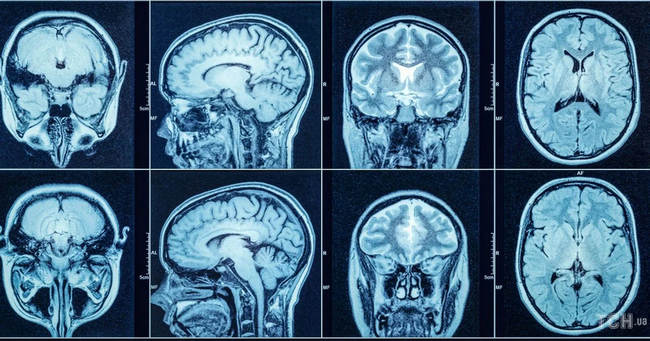

Нейрохірурги пояснюють: під час МРТ-сканування вас попросять лягти у довгий відкритий тунель, який має назву МРТ-сканер. Він використовує радіохвилі, які відбиваються від молекул жиру та води у вашому тілі. Ці сигнали надсилаються на комп’ютер для створення зображення ураженої ділянки. МРТ використовується, щоб подивитися стан м’яких тканин. Наприклад, спинний мозок, нерви, зв’язки або різні стенози.

Лікарі наголошують: КТ — це той самий рентген, але набагато потужніший, це — опромінення. МРТ працює інакше: у ній реєструються атоми водню і вона безпечніша, тож МРТ можна робити стільки разів, скільки необхідно.

МРТ-сканування зазвичай коштує дорожче, ніж КТ, і надає більш детальні зображення. Але справа не в тому, що один метод кращий за інший, а скоріше — який метод краще відповідає конкретним потребам пацієнта.